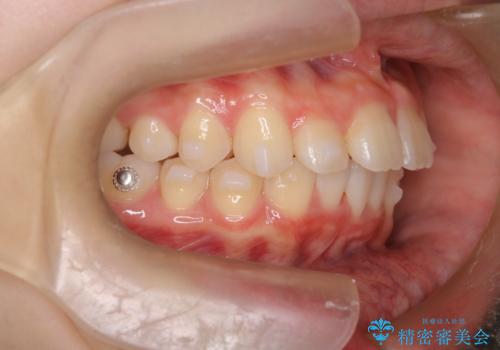

- 前歯が出ていることを主訴に来院されました。

下顎前歯が1本欠損していることもあり、前突はある程度残ることを説明し、インビザラインにて治療を行いました。

今回は抜歯矯正ではなく歯列弓の拡大とIPR、遠心移動を行って配列することができました。

口元も改善し患者さんには喜んでいただけました。

下顎前歯が1本少ないため、上下の正中は合いません。